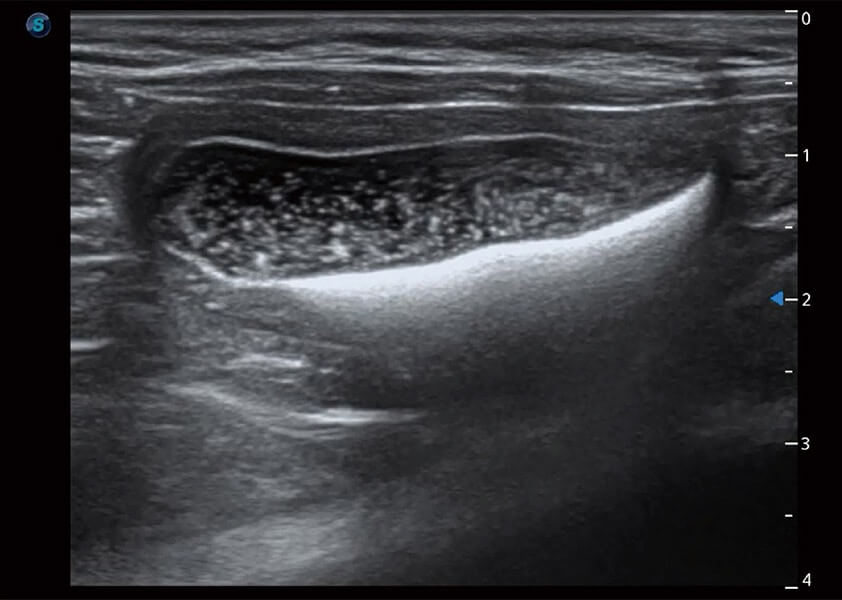

ProPet 60 作为一款高端台式动物超声设备,为动物医生的日常诊断提供了一系列贴合动物临床需求、解决临床实际问题的高级成像功能。凭借全系列高清探头,满足医生对腹部、心脏、生殖、浅表、肌骨等成像的所有需求,切实帮助您提升检查效率,提高诊断信心。

动物是人类最亲密的朋友和最值得信赖的伙伴。亚星官网也一直致力于探索动物专用的超声影像解决方案。 全新推出的ProPet系列,是亚星官网在动物超声影像智能化、专业化、精准化的一次跨越式革新。动物不能用言语来表述自己的不适,通过超声影像,ProPet系列搭建了动物医生与不同物种沟通的“桥梁”,为动物医生注入了“治愈之力”。